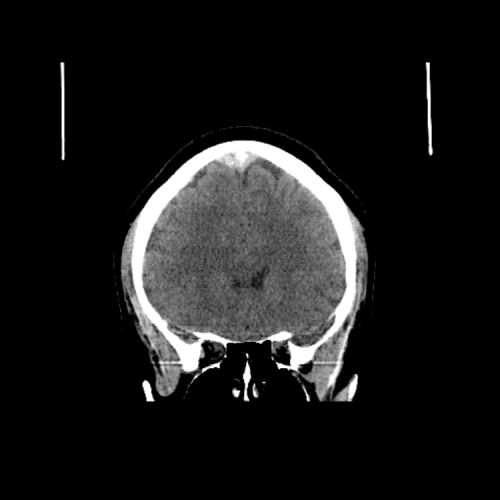

ACA and MCA territory infarct